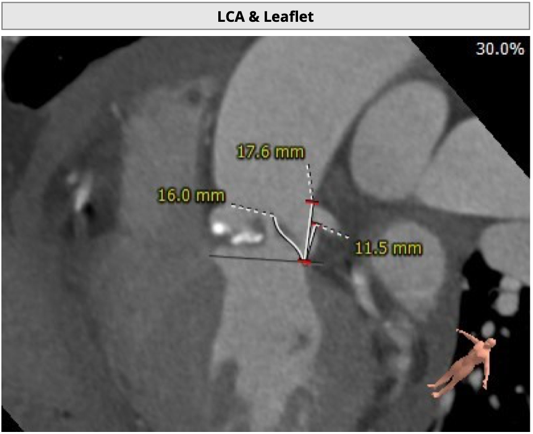

主动脉根部评估

CT 数据显示该患者为三叶式主动脉瓣

主动脉瓣瓣环周长75.6mm,周长径24.1mm;

LVOT 周长 74.1mm,周长径23.6mm;

SOV:28.5mm*31.6mm*29.4mm;

STJ 周长 93.9mm;

HU850:87mm³;

瓣环水平夹角52度。

TaurusNXT植入过程

考虑患者左冠开口偏低,左瓣叶冗余影响左冠血流,预置GuidezillaII支撑保护,之后采用TaurusAtlas 22mm球囊预扩张,植入AV26 TaurusNXT主动脉瓣,起搏140次/分频率下,在左右重合位瓣膜释放达到工作位,造影显示锚定位置理想,之后在右窦中心位下再次确认植入位置,同时超声评价瓣膜位置及血流动力学情况,最终0位精准释放瓣膜。无回收,无球囊后扩张,未植入冠脉支架。术后即刻超声心动图评估显示瓣膜位置良好,微量瓣周漏,主动脉瓣口峰值流速为1.80m/s,平均跨瓣压差为5mmHg,有效瓣口面积 2.4cm2,血流动力学指标理想。在线专家称赞陈绍良教授、张俊杰教授团队完美完成了一例高冠脉风险、重度主动脉瓣狭窄TAVI手术。